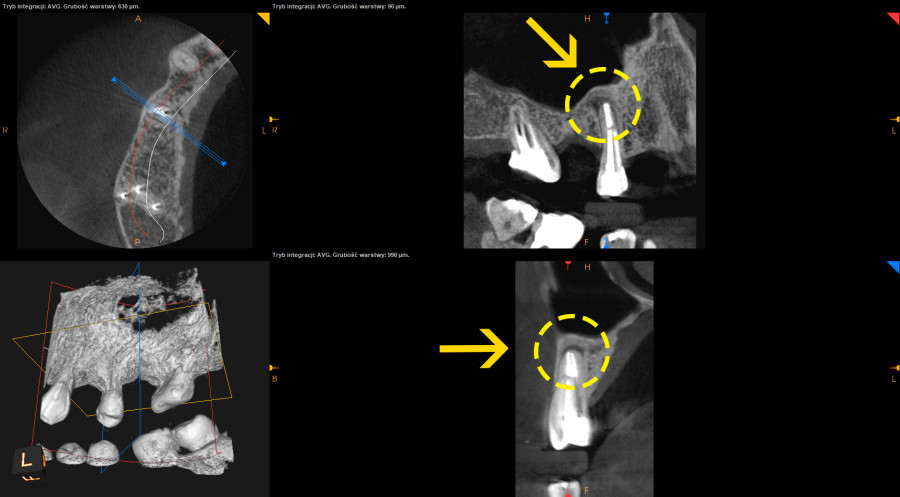

- Wykonanie nowoczesnej diagnostyki pozwoliło na znacznie szybszą ocenę gojenia w stosunku do prześwietleń takich jak ortopantomogram lub radiowizjografia i skróciło okres obserwacji gojenia.

- Pacjent juz po 4 miesiąch od leczenia endodontycznego mógł wrócic do protetyka celem wykonania mostu porcelanowego.